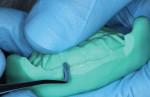

A silicone matrix was fabricated upon completion of a waxed proposal of the desired length increase for the central incisors (Figure 3 and Figure 4).2 The central incisors were prepared for the bonding procedure by irregular bevel placement with diamond instrumentation to aid in marginal blend (Figure 5).3 To maximize adhesive values, the prepared surfaces were air abraded with 50-µm aluminum oxide.4 Total etch with 37% phosphoric acid preceded application and light-curing of a universal adhesive (Futurabond U®, Voco Corp.).

The ORMOCER restorative (Admira Fusion) was placed via a systematic lingual-to-buccal layering technique of the relevant universal (A1) and translucent (incisal and bleach) shades for optimal blending and optical characterization (Figure 6 and Figure 7).5-7 The restorations were shaped, finished, and polished using a conventional sequencing of instruments, including fluted carbides, finishing discs, silicone polishers, and abrasive brushes (Figure 8). Restoration of the right central incisor was completed first, and the steps were repeated for restoration of the left central incisor, and desired length increase was achieved (Figure 9 through Figure 11).